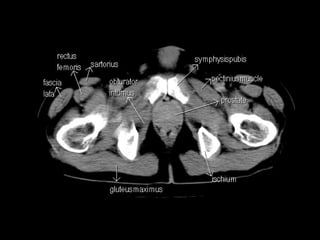

Radiographers use medical imaging equipment like X-rays and MRIs to produce images of patients' internal structures and organs. They are responsible for positioning patients, operating scanning machines, and ensuring quality images. Radiographers must have strong attention to detail, excellent communication skills, and the ability to work well under pressure to accurately capture anatomical features and diagnose any abnormalities.